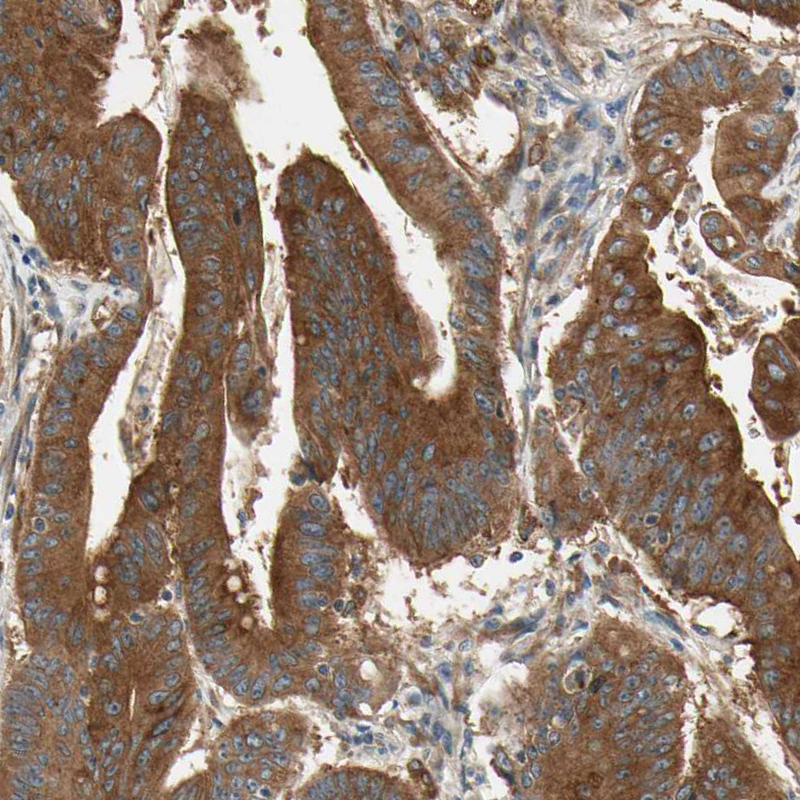

Immunohistochemical staining of human colorectal cancer shows strong cytoplasmic positivity in tumor cells.